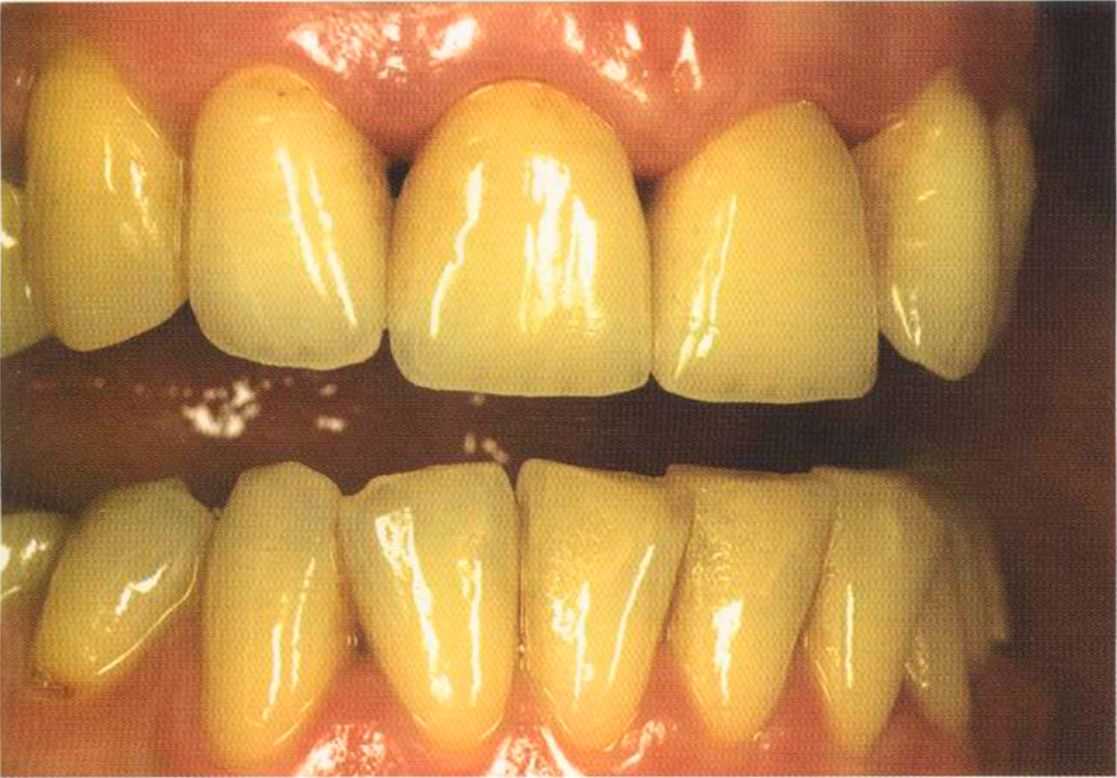

Отмечаем, что десна здоровая. Она гармонирует с коронкой ln-Сегат за счет отличных свойств материала

и отличного краевого прилегания.

Теперь коронки в области боковой группы зубов не нравятся, и в скором времени их тоже будем переделывать.

Коронки выполнялись в моей лаборатории вместе с пациентом. Мы работали долгих четыре часа, чтобы всем понравился результат. Обратите внимание на отражение света по краевым валикам. Мезиальные валики коронки 12 зуба гармонично переходят в дистальные валики 42 зуба. В идеальном варианте «отражающиеся валики» должны проходить по прямой линии. Это привило для всех мезиальных и дистальных валиков фронтальной группы зубов. Оно имеет очень важное значение и влияет на результат нашей работы.